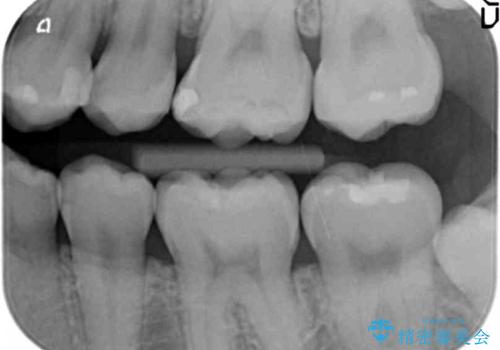

奥歯の虫歯治療でしたが、プラスチック周りと、歯と歯の間が大きな虫歯になっていました。

インレーでの修復予定でしたが、歯と歯の間が狭く、正確な型取りが難しい状態でした。